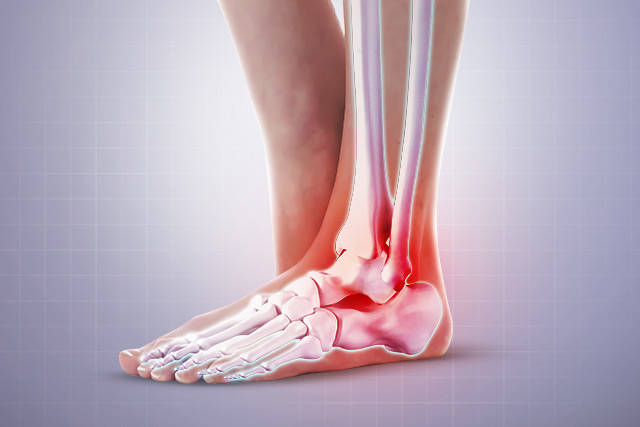

족저 근막은 종골에서 시작하여 발바닥 앞쪽으로 5개의 분지를 내어 발가락 기저부에 부착되는 강인하고 두꺼운 섬유 띠입니다.

이는 발의 아치를 유지하고 체중 부하 상태에서 발을 올리는데 도움을 줍니다. 족저 근막염은 족저 근막에 미세한 손상이 반복해서 발생하여 콜라겐이 변성되고 퇴행성 변화로 통증이 유발되는 질환입니다.

가장 흔하게 나타나는 족부 병변 중 하나로 뒤꿈치의 통증을 일으키는 질환입니다. 장시간 서있거나 과도한 운동 , 몸무게 증가, 하이힐 등 발에 스트레스가 증가하면 더 쉽게 발병합니다.